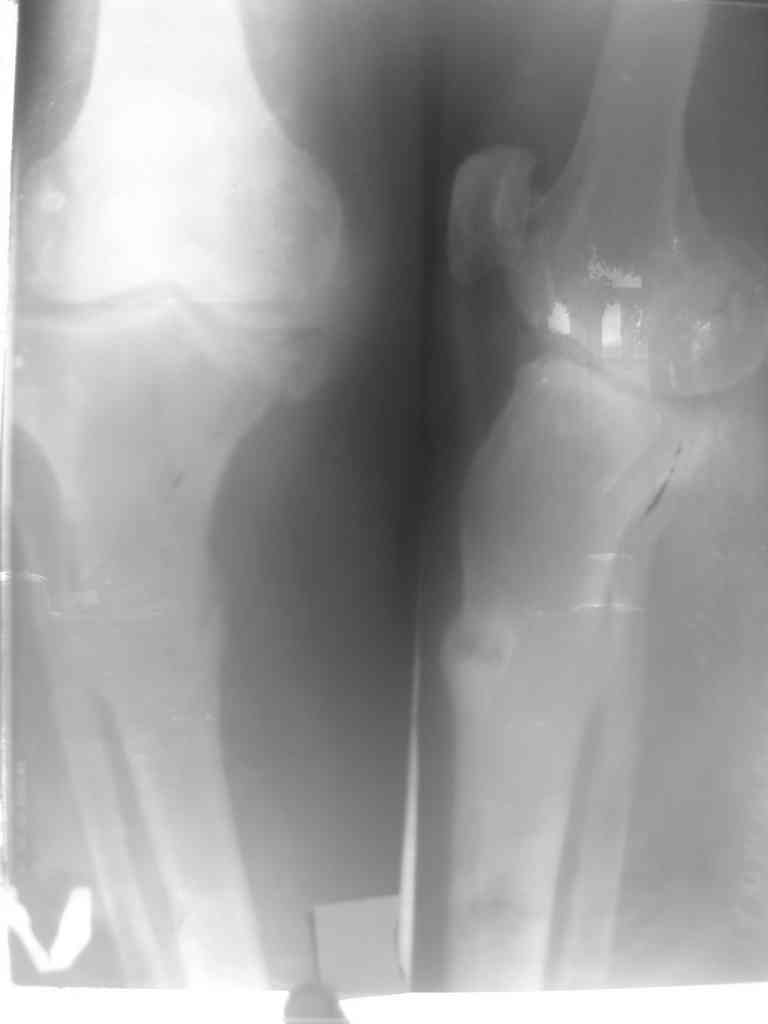

Глубокоуважаемые коллеги! Женшина 67лет.6месяцев назад упала.

после этого с болями но ходила с палочкой. постепенно появилась варусная деформация. боли усиливались. ходить стало трудно. Возможно это последствие остеопоротического перелома - ложный сустав? тактика лечения? Рентген снимок не очень качественная .

На снимках, кроме деформации большеберцовой, мне кажется, имеется медиальный артроз коленного сустава.

Невозможно определить четко, что это медиальный коллапсированный остеофит, или его перелом?

Сравнительные снимки колена и снимки всей длины конечности подтвердит диагноз артроза и также подскажет истинное нарушение оси конечности.

При прохождении оси конечности медиально, невозможно решить проблему только коррегированием оси большеберцовой.

Изначальное отсутствие сиптомов можно обьяснить тем, что несмещенный перелом возможно в "виде трещины" вторично сместился при нагрузке из-за варусного нарушения оси конечности.

1. Действительно, у больной двух сторон. пателло-феморал и тибио-феморал. артроз с остеофитами. Но ось прав н/к правильный, а слева в обл.ложного сустава имеется деформация. Фото прилагается.